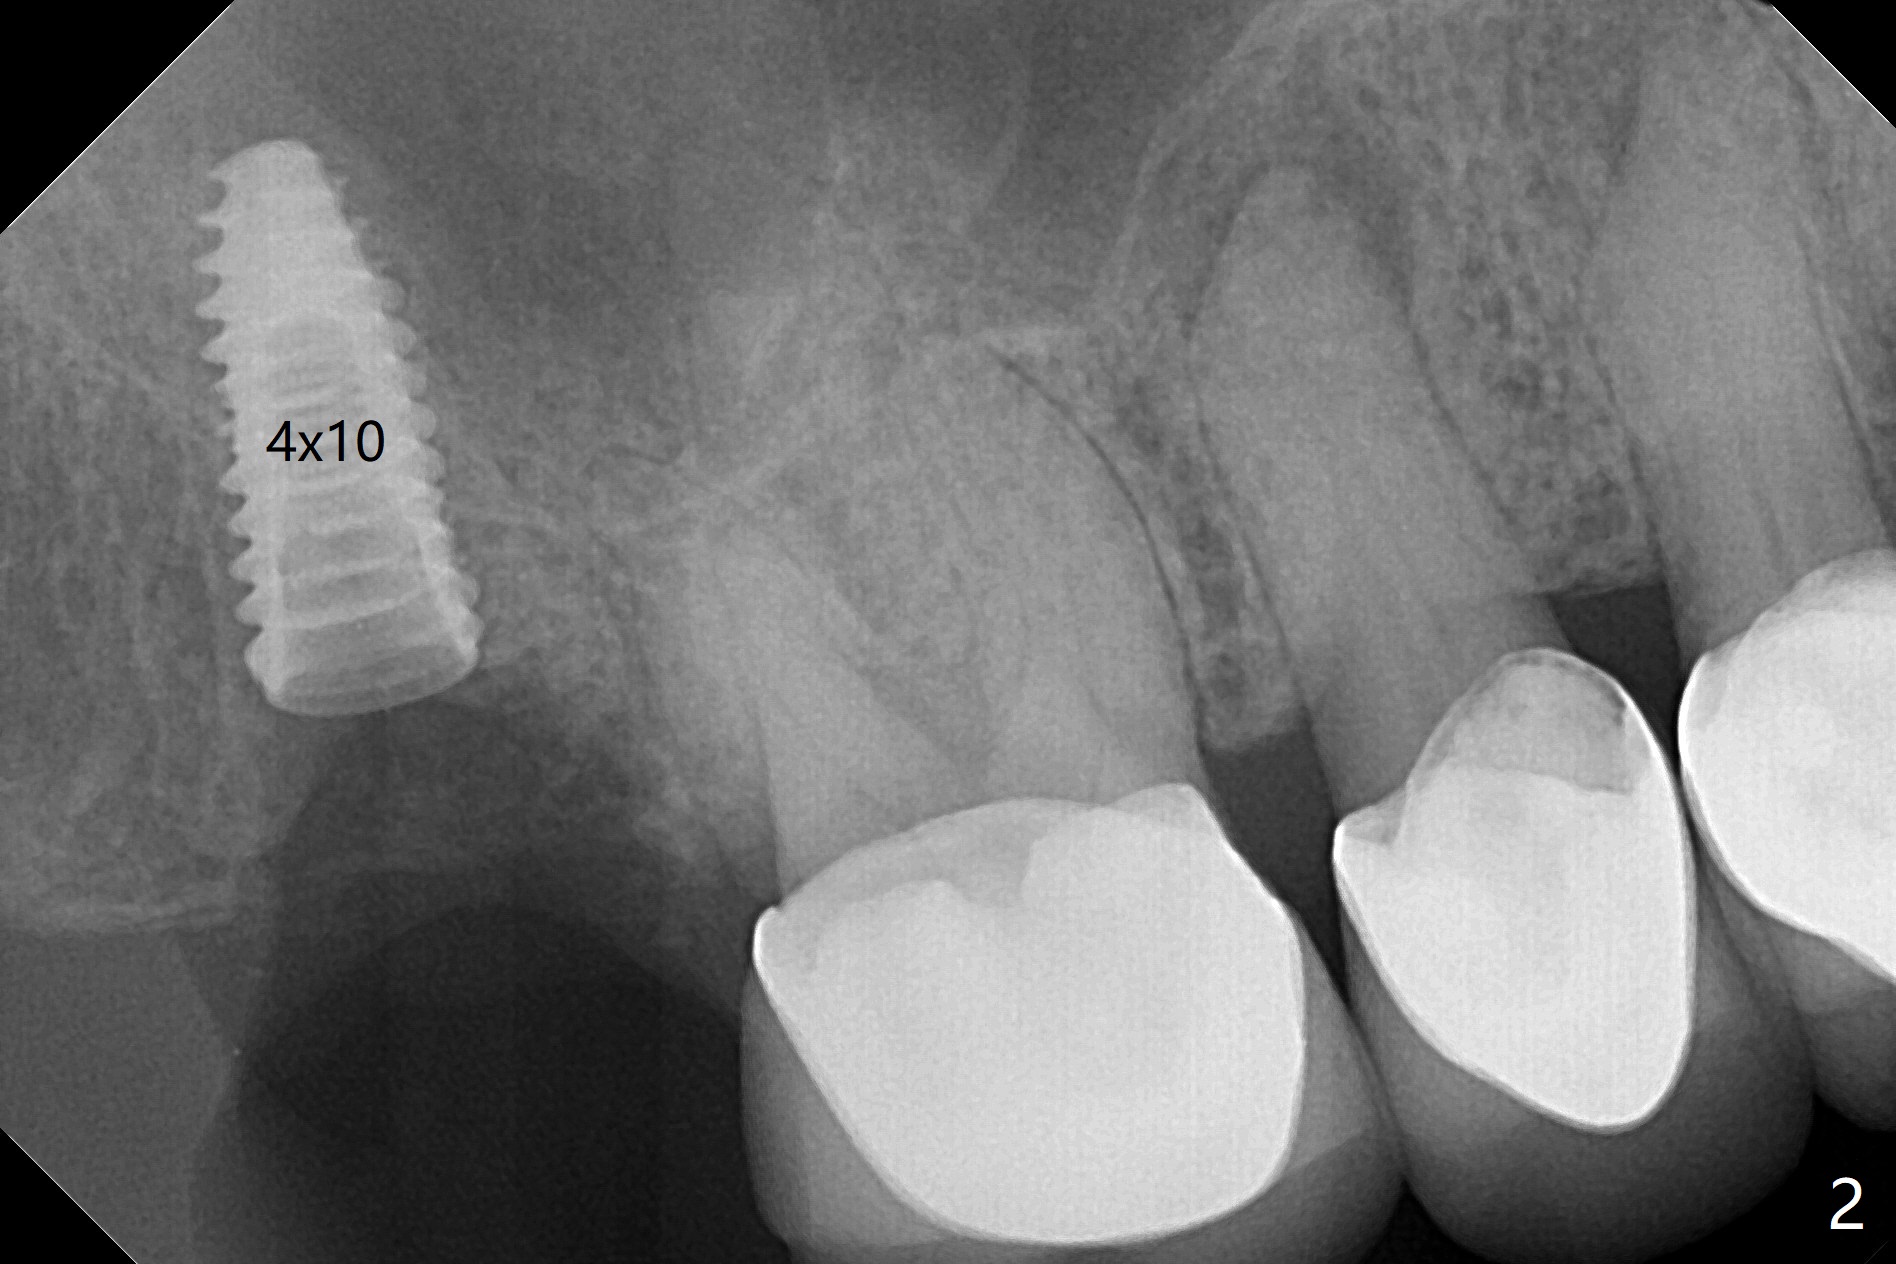

When the tooth #2 is extracted, there is sinus perforation in the palatal apex, consistent with preop CT (Fig.1: P). There is no bone shaving associated with drill sequence in the buccal socket (until 3.5x8.5 mm). With sticky bone and 4.5x10 mm IS dummy implant, sinus lift does not happen. Sinus floor perforation is felt when a 2.2x10 mm drill is used slowly. But air leaks from the palatal socket. With bone graft, a 4x10 mm dummy implant lifts the sinus (Fig.2). After further graft and 4.5x10 mm dummy implant, a 5x11 mm final implant is placed with 15 Ncm with sinus lift (Fig.3,4 *). Following abutment insertion, sticky bone is packed around the implant and abutment (Fig.5,6 S). Prior to final implant placement, a small piece of PRF and collagen and Osteogen Plugs are placed in the palatal socket for repair. Before discharge, there is mild nasal hemorrhage.